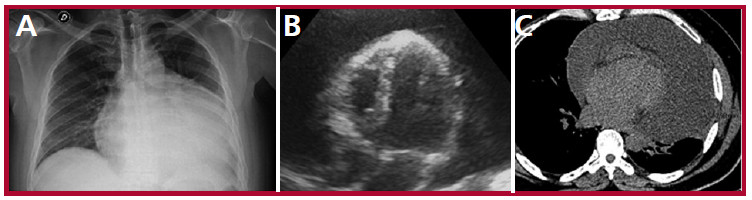

En el laboratorio no se evidenciaron alteraciones de relevancia (Hematocrito 45%, Creatinina 1,2 mg/ dL; urea 25 mg/dL; plaquetas 240mil/mm3, leucocitos 9100/mm3). El electrocardiograma mostró taquicardia sinusal, con complejos QRS de bajo voltaje y en la radiografía de tórax se evidenció aumento del índice cardiotorácico, con imagen en botellón (Figura 1, A).

Se realizó un ecocardiograma Doppler junto a la cama el paciente, que evidenció derrame pericárdico grave circunferencial, con máxima separación entre hojas de 7,5 mm, función ventricular izquierda conservada, colapso de cavidades derechas y vena cava inferior dilatada (Figura 1, B). Ante dichos hallazgos se decidió realización de drenaje pericárdico de emergencia, y se extrajeron 2,2 litros de líquido citrino.

Una vez estabilizado, se solicitó una tomografía de tórax que excluyó calcificación pericárdica y mostró derrame pericárdico leve a moderado, asociado a atelectasia pasiva del parénquima pulmonar izquierdo (Figura 1, C). Se completó evaluación mediante resonancia magnética nuclear cardíaca, donde se observaron volúmenes, espesores parietales y fracción de eyección del ventrículo izquierdo conservadas, deterioro de la fracción de eyección del ventrículo derecho con dilatación del mismo, dilatación biauricular, derrame pericárdico moderado y aplanamiento sistólico del septum interventricular (acentuado luego de inspiración forzada). Se observó realce tardío de gadolinio a nivel del pericardio (Figura 2, A, B y C). Dichos hallazgos fueron compatibles con la presencia de una pericarditis efuso-constrictiva.